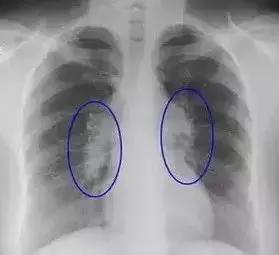

肺部结节

一般年龄大、肺部有基础疾病的人,做检查易发现肺部结节。即使发现肺部结节也不必恐慌,因为其中只有极少部分人最后被证实是肺癌。

此时必须找专业医生鉴别判断:对于小于5毫米的微小结节,仅做随访观察,3个月到半年重新做一次CT检查。如结节没有变化、没有异常增大,一般被认为是没有风险的,有的甚至会随着时间变化慢慢消失。1厘米以上的大结节,建议要尽早诊治。